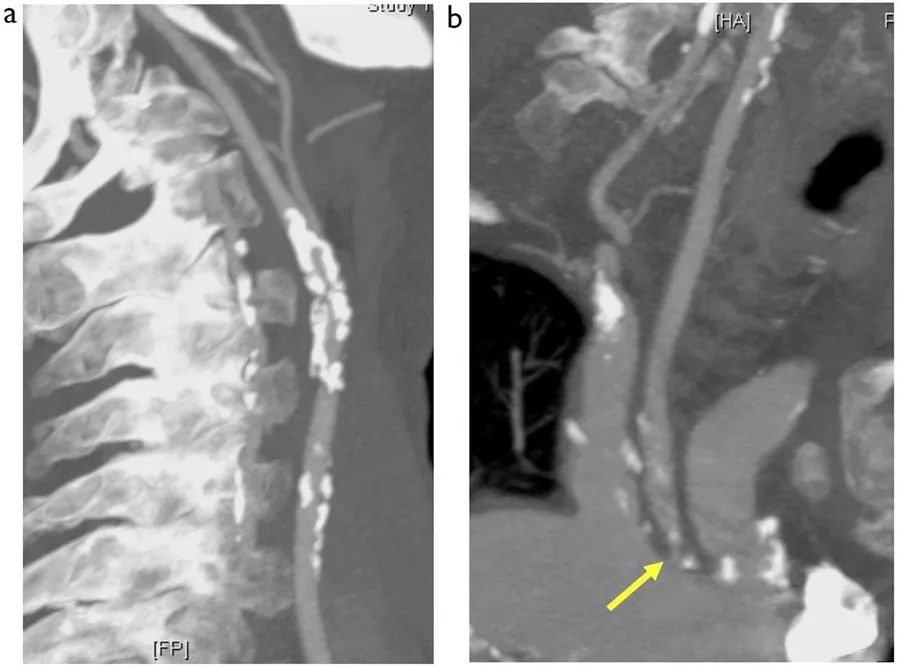

图8  65岁男性,左侧大脑半球短暂性脑缺血发作,图为包括主动脉弓、颈部和颅内动脉的CTA,A:斜冠状位;B:矢状位;C:斜矢状位

不难看出,本例患者左颈动脉球和颈内动脉起始处可见严重不规则狭窄,而这也是患者出现短暂性脑缺血发作的罪魁祸首。